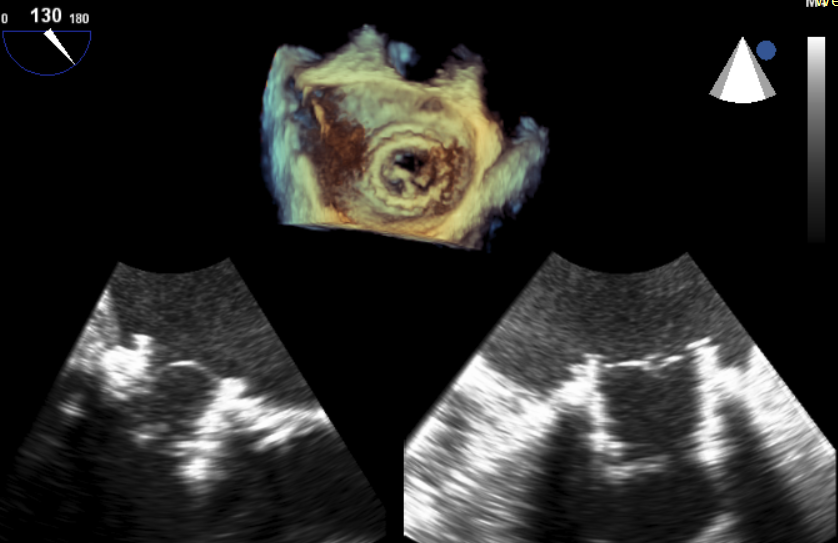

术中影像监护与评估(DSA&TEE)

原生物瓣少量反流

过瓣流增快,呈“五彩状”

CDFI提示过瓣血流通畅

CDFI示少量瓣周漏